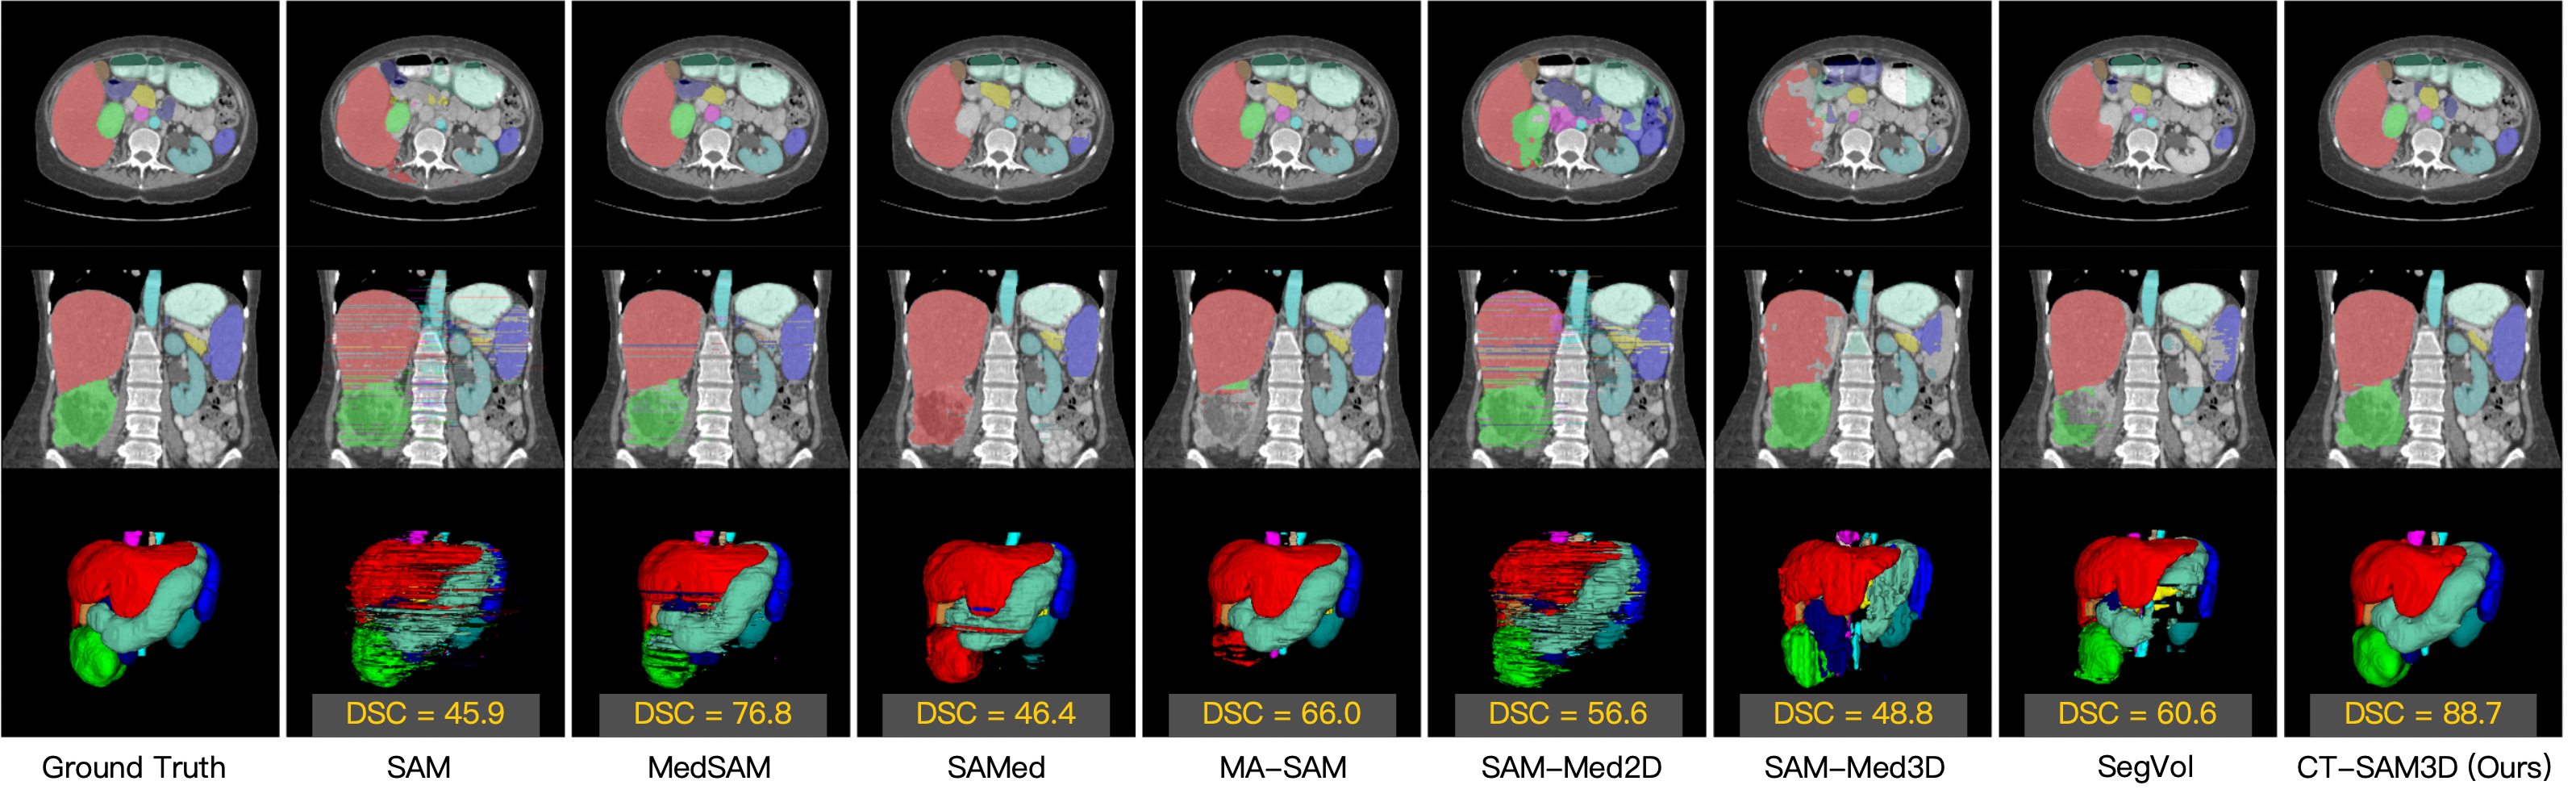

Refer to caption

Figure 5: Qualitative results of different methods on a subject who exhibits severe renal pathology (green region). The first row is an axial slice, the second row is a coronal slice, and the last row shows the 3D volume rendering. DSC (%) scores are mentioned for each method.

External testing on FLARE22 is summarized in Table 1 and  Fig. 4.  Table 1 presents the detailed organ-wise segmentation results when the prompt number N=5𝑁5N=5italic_N = 5, while Fig. 4 illustrates the organ-averaged segmentation accuracy with respect to the prompt number N𝑁Nitalic_N, as N𝑁Nitalic_N varies from 1 to 9. As shown in Table 1 and Fig. 4, the proposed CT-SAM3D generalizes well to the external testing and performs significantly better as compared to other SAM-derived models with a large margin of >absentsimilar-to>\sim> ∼10% DSC and >absentsimilar-to>\sim> ∼15% NSD. Several interesting observations can be made. 1) The very recent 3D SAM models (SAM-Med3D and SegVol) do not generalize well, although they are trained on 21K21𝐾21K21 italic_K and 6K6𝐾6K6 italic_K medical images respectively. 2) Although SAMed and MA-SAM disable the prompt encoding module, they achieve the 2nd and 3rd best accuracy (if not considering the missing targets). This demonstrates the effectiveness of adaptation methods to some degree. However, these adaptation methods target on segmenting only a small fixed number of organs, limiting their general interactive segmentation ability. 3) We see from Fig. 4 that with more point prompts, CT-SAM3D’s segmentation accuracy continues to increase, illustrating its interactive segmentation capacity. In contrast, with even 9 prompts per input sample, other methods still obtain undesirable segmentation accuracy, ranging from 55% to 75% DSC or from 50% to 85% NSD. 4) Not all methods improve consistently when the number of clicks increases, e.g., MedSAM starts to degrade when N>3𝑁3N>3italic_N > 3, indicating its deficiency in understanding/encoding user’s prompts. A qualitative example is shown in Fig. 5.